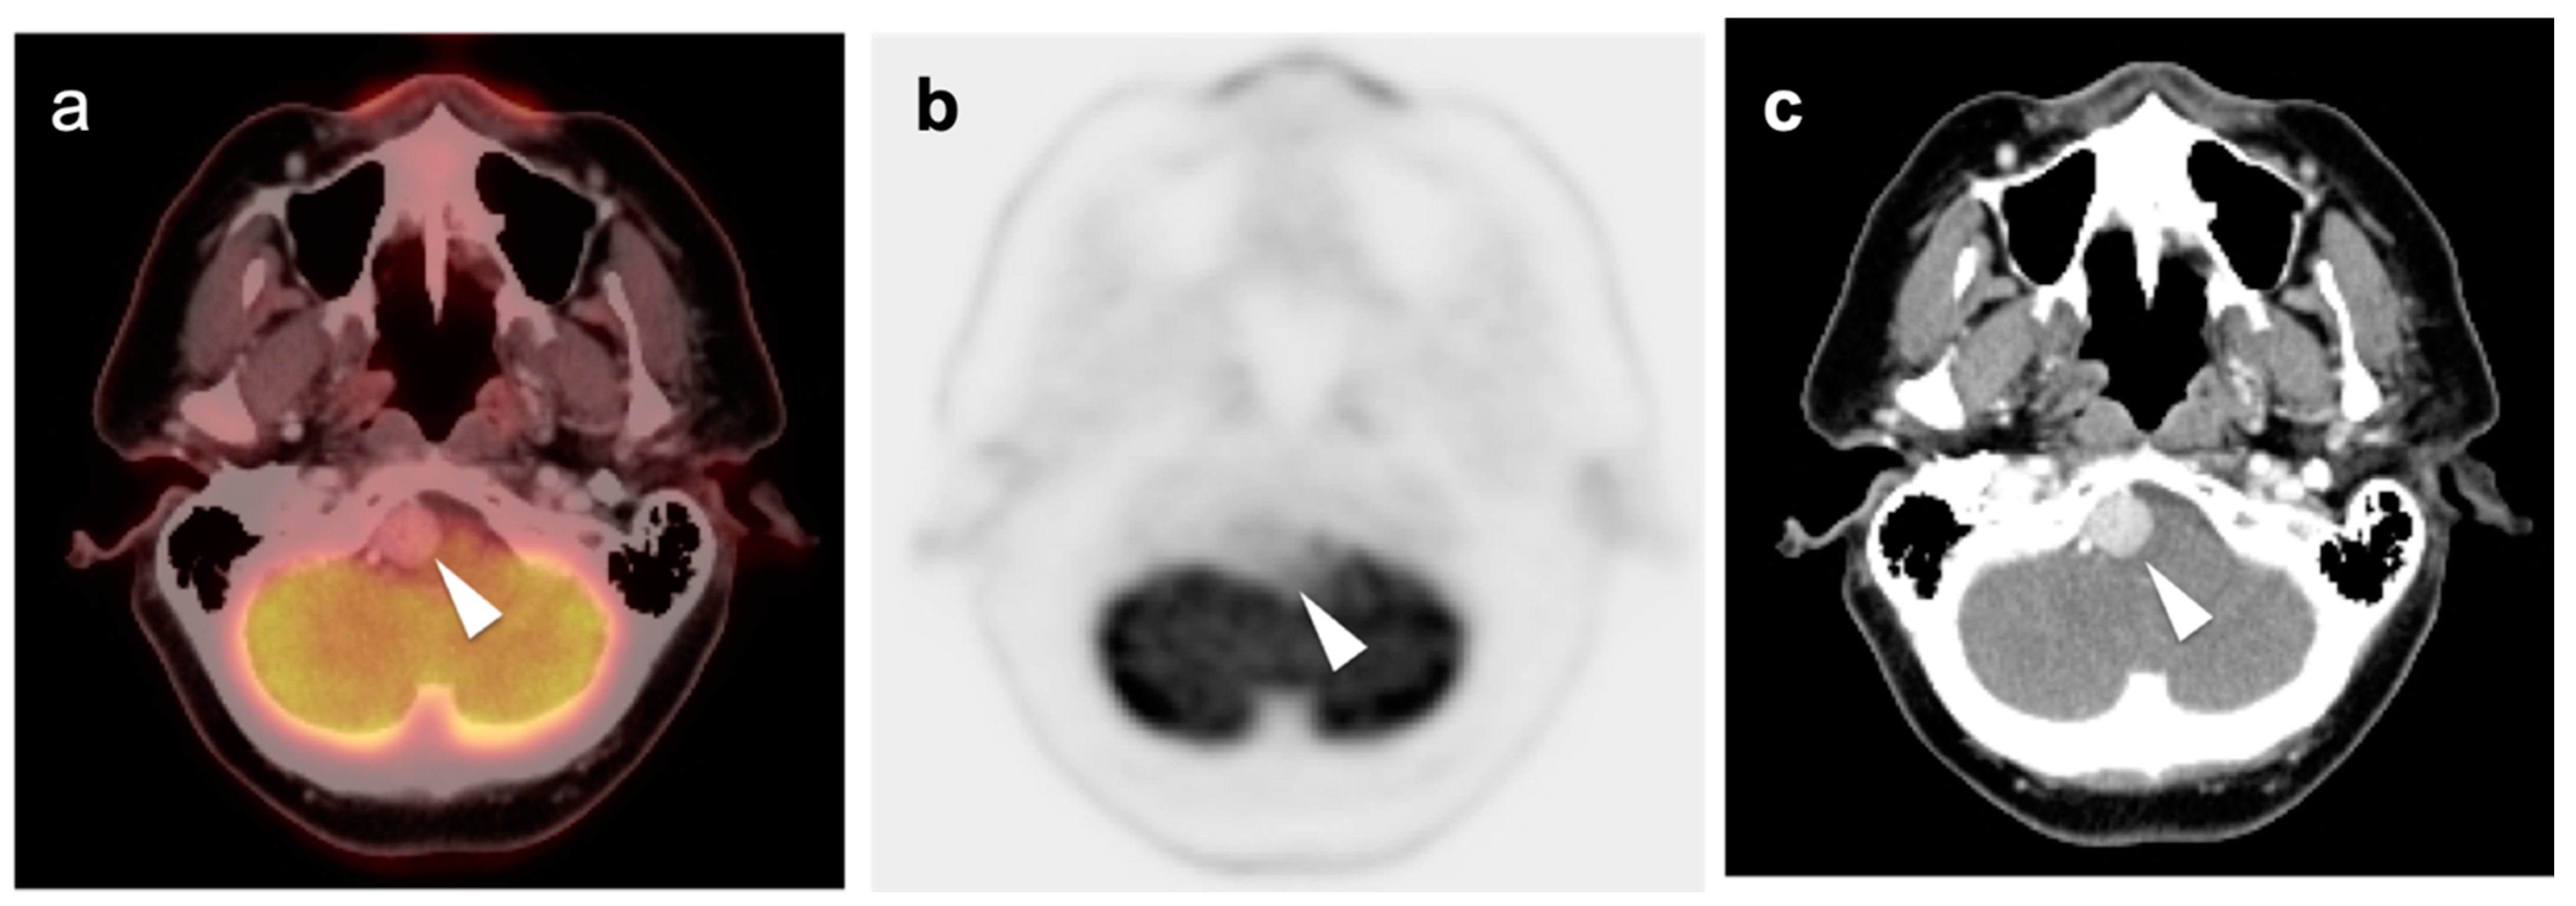

2.3. Nasopharyngeal Carcinoma